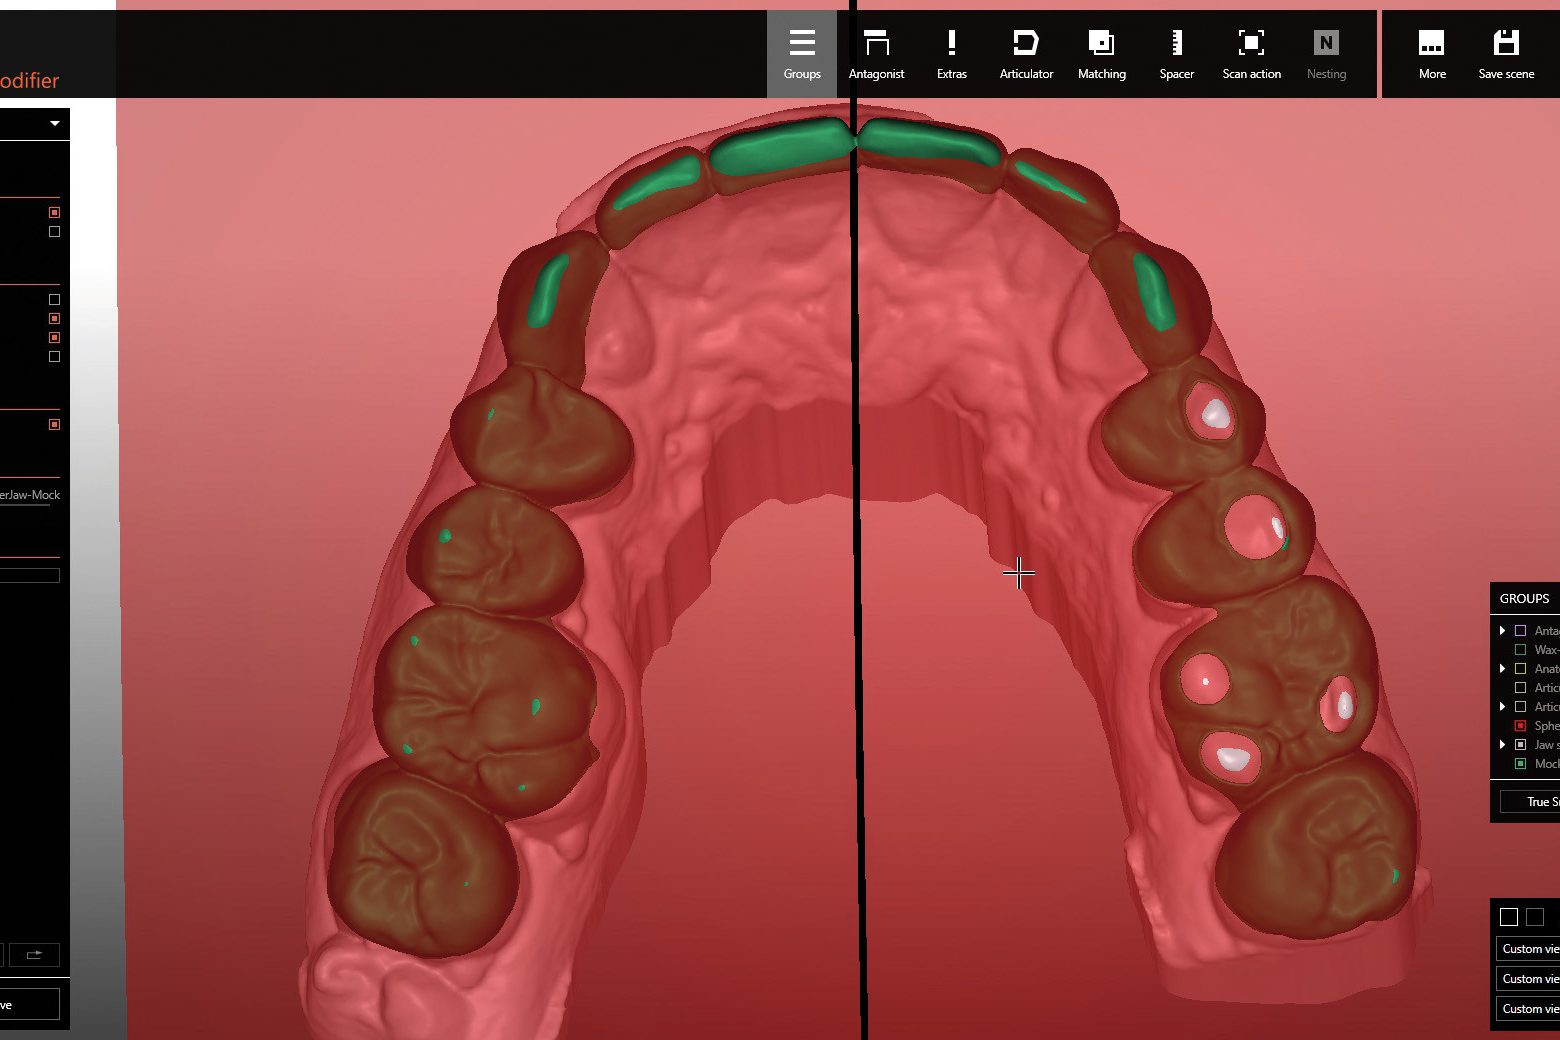

- Digital tooth set-up in the Zirkonzahn.Modifier software using the DEMI tooth set from the Heroes Collection virtual library; tooth individualisation

- Design and milling of a digital block-out model for the upper and lower mock-ups in Temp Premium Flexible

- Based on the patient-specific model articulation and the selection of a digital Monsons Sphere with Ø 240 mm, the areas to be prepared in the occlusal region were highlighted and a preparation guide for the upper jaw was created. After determining the centric relationship, it turned out that, due to the new occlusal height, the canine 23 needed a palatal support surface to optimise function. Therefore, a vestibular and a palatal veneer were designed to avoid too invasive preparation of the natural tooth. During cementation, the vestibular veneer was applied first, and then the palatal one (‘sandwich technique’)